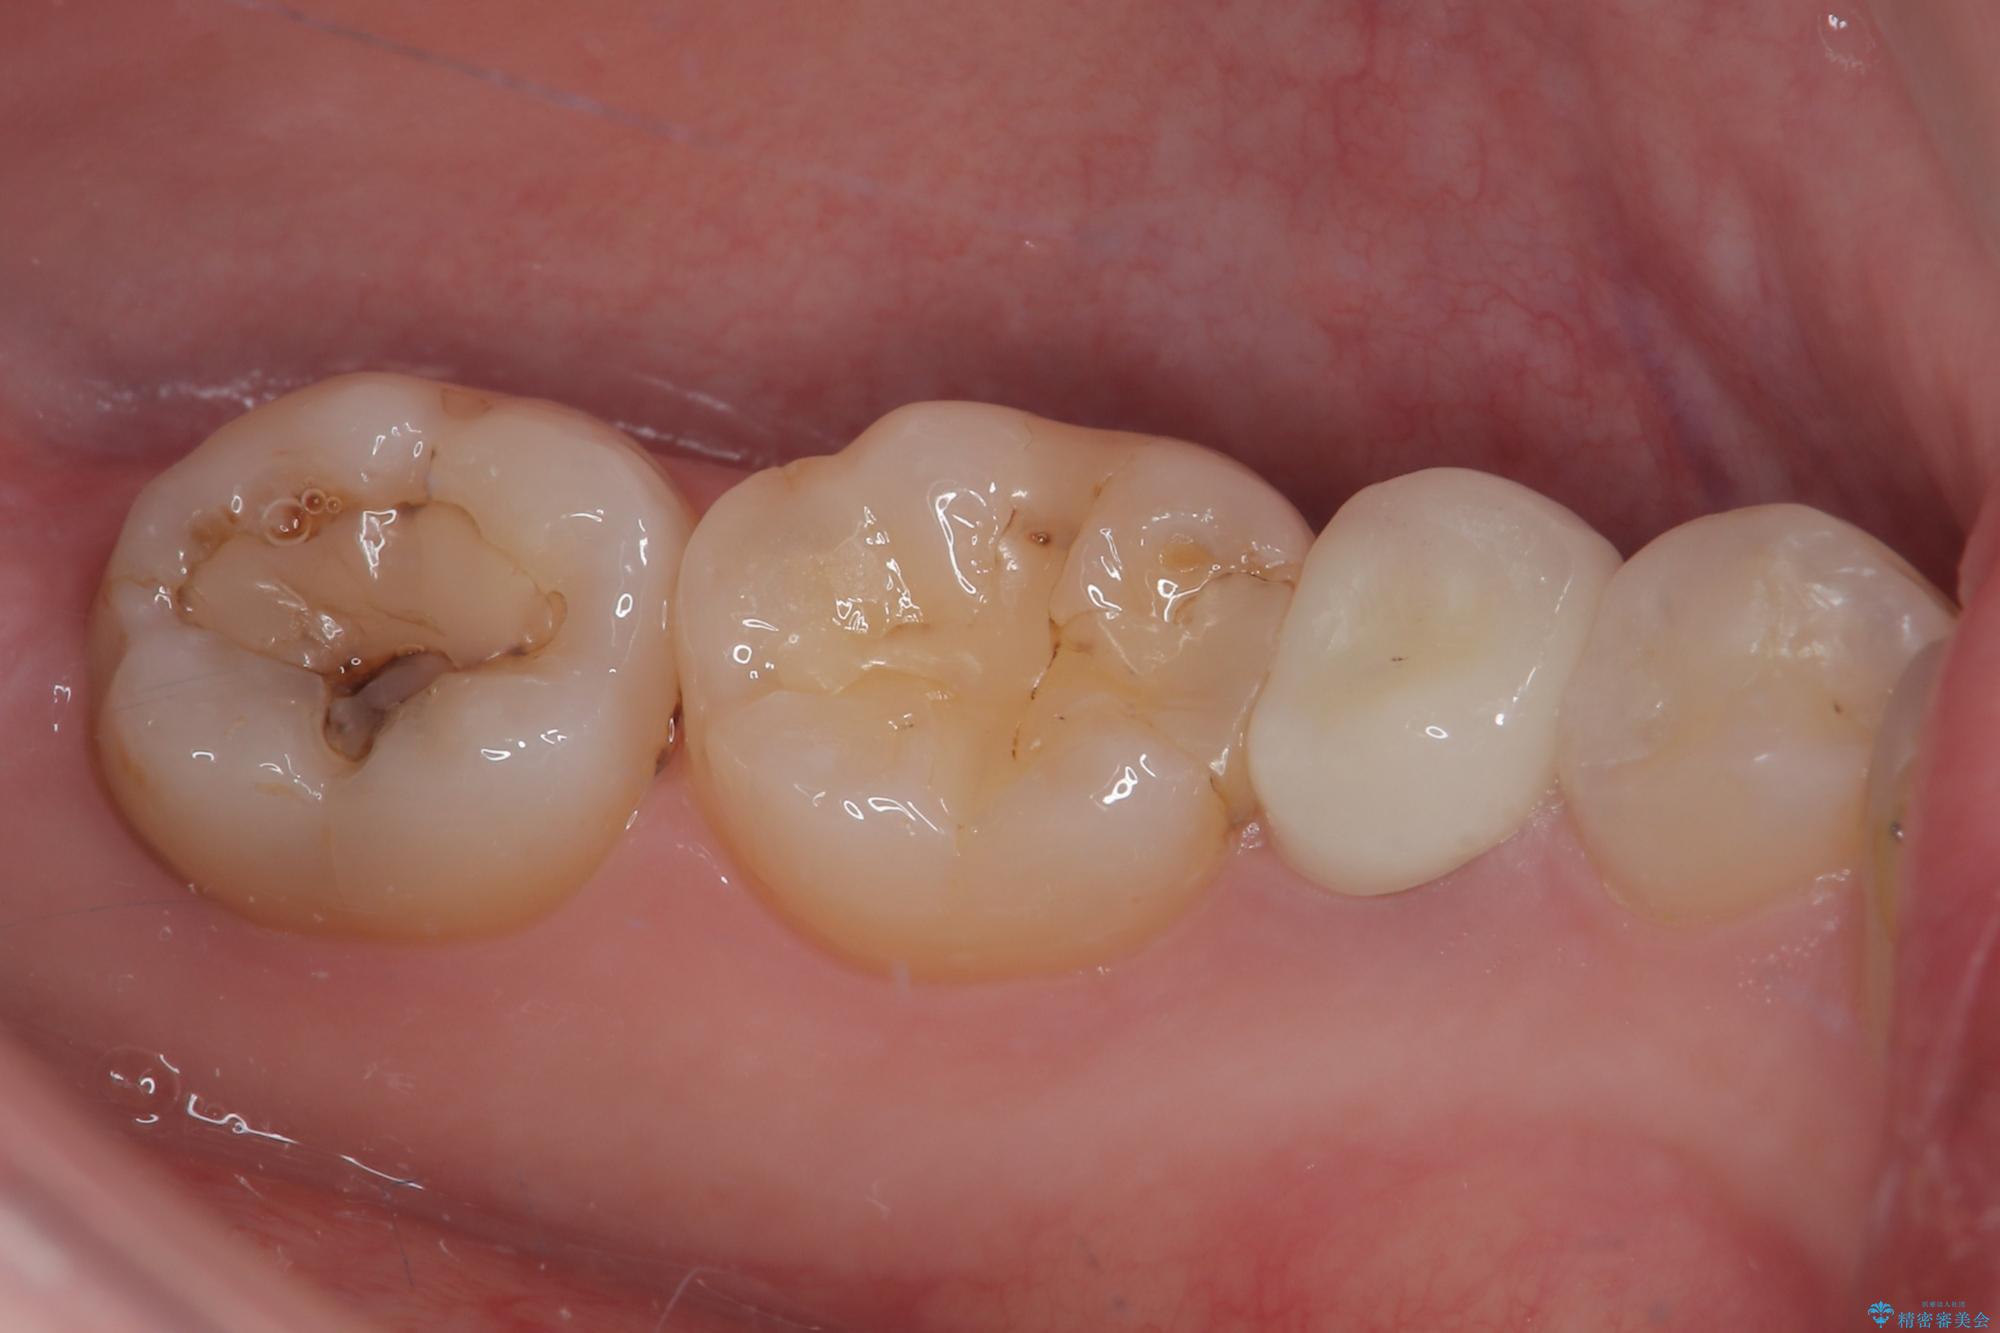

- 左下の被せものが割れたとのことで来院された患者様です。検査の結果、左下の前から4番目の歯はセラミックインレー修復、左下の5番目のところはオールセラミッククラウンによる補綴治療を行っていくことにしました。

拡大鏡視野下で被せもの、虫歯の除去を行い、オールセラミッククラウン、セラミックインレーに適した形に整えました。

適合の良い被せものが入り、審美面も気に入っていただけました。被せものが割れていたという経緯もあったため少しだけ被せものの厚みを多めに確保してあります。